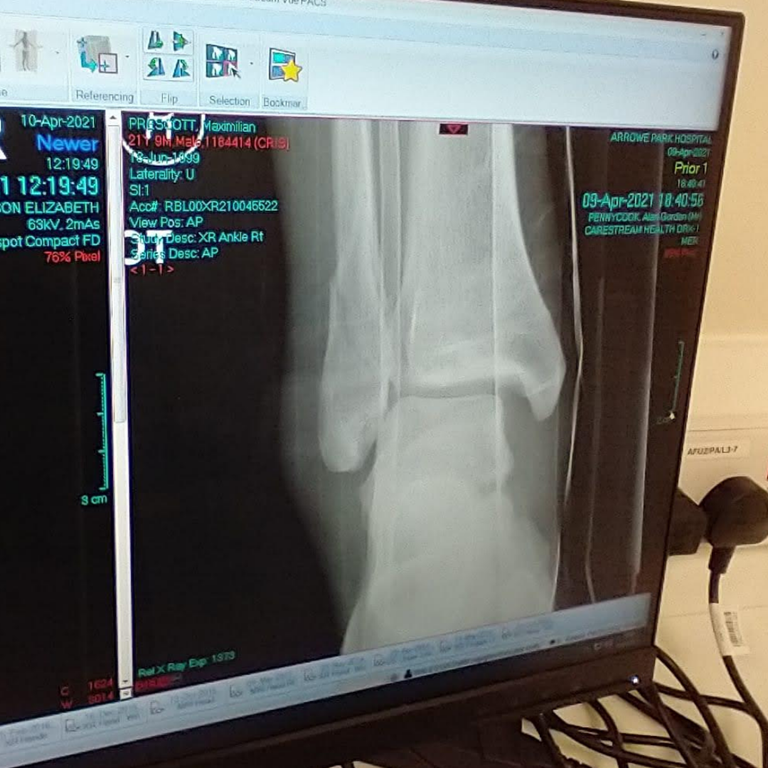

My parents bought me a skateboard for one skateboarding lesson I had when I was younger, but that about summarises my history with the sport. I thought it would never be used again. However, we were just beginning to ease out of the third lockdown, and my friend and I sought to cure our lockdown fatigue with a trip to the local skatepark. I dusted off the old skateboard and we hit the ramps. We’d only been there twenty minutes, and I thought the next progression would be to drop in on a (small) half-pipe… I think you can already see where this is going to go wrong. I had the skateboard hovering over the edge of the ramp, and after one deep breathe, I thought ‘F*** it’ and leant forward. But my instincts betrayed me, I immediately recoiled, sending the skateboard flying and landing in an awkward heap on my right leg. I knew it was broken immediately. Picture 1 shows the scene when the paramedics arrived.

I broke two bones in my ankle and ruptured my deltoid ligament, meaning it was an unstable ankle fracture and would require surgery (see Picture 2). I was told it would be a good outcome if I could walk again without pain. The first two weeks were all about managing pain, resting, and keeping the ankle elevated to reduce the swelling for the surgery. After the surgery, the following two weeks were much of the same until the cast could be removed. Essentially, I would spend the whole day in bed only getting up to make food or go to the bathroom.